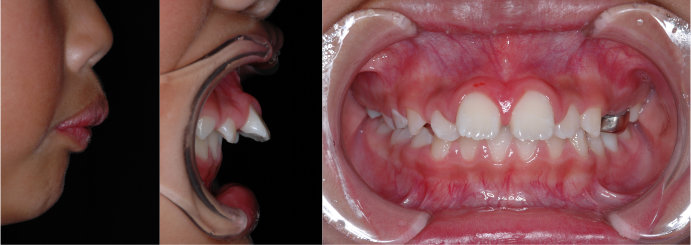

| Case3 |

| 受け口 |

| <治療前> |

| <治療後> |

| 主訴 |

上の歯がねじれている |

| 診断名 |

叢生を伴う反対咬合 |

| 年齢 |

10歳 |

| 使用装置 |

マルチブラケット装置 |

| 抜歯部位 |

永久歯の抜歯は無し |

| 治療期間 |

3年6か月 |

| 治療費概算 |

検査・診断料:5万円+税 装置・技術料:25万円+税 おおよそ1か月ごとの処置・管理料:5,000円+税 保定装置料:5万円+税 |

| リスク・副作用 |

う蝕 |